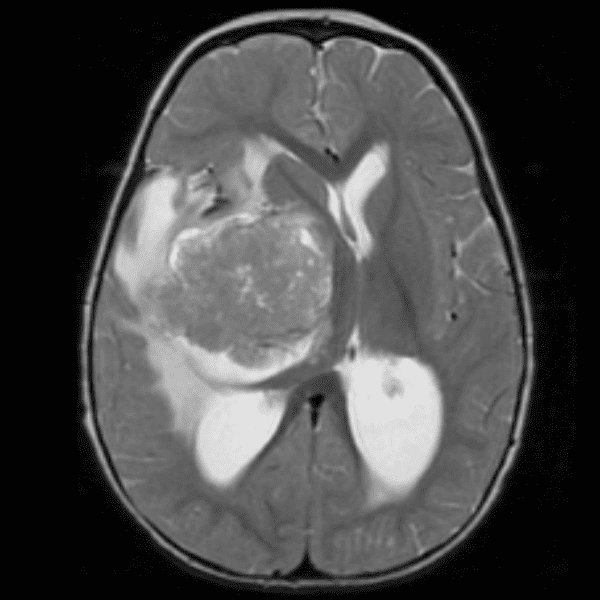

Classic Cases